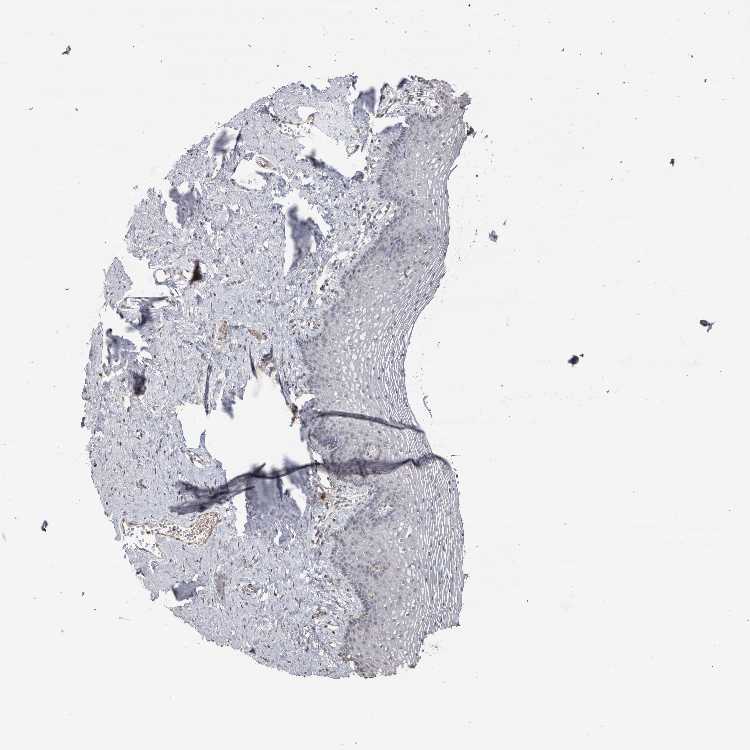

VAGINA - Antibody stainingi

Antibody staining in the annotated cell types in the current human tissue is reported as not detected, low, medium, or high, based on conventional immunohistochemistry profiling in selected tissues. This score is based on the combination of the staining intensity and fraction of stained cells.

Each image is clickable and will lead to virtual microscopy that enables deeper exploration of all samples and also displays staining intensity scores, fraction scores and subcellular localization as well as patient and tissue information for each sample.

Antibody HPA000603Antibody CAB025604

Squamous epithelial cells Not detectedLow